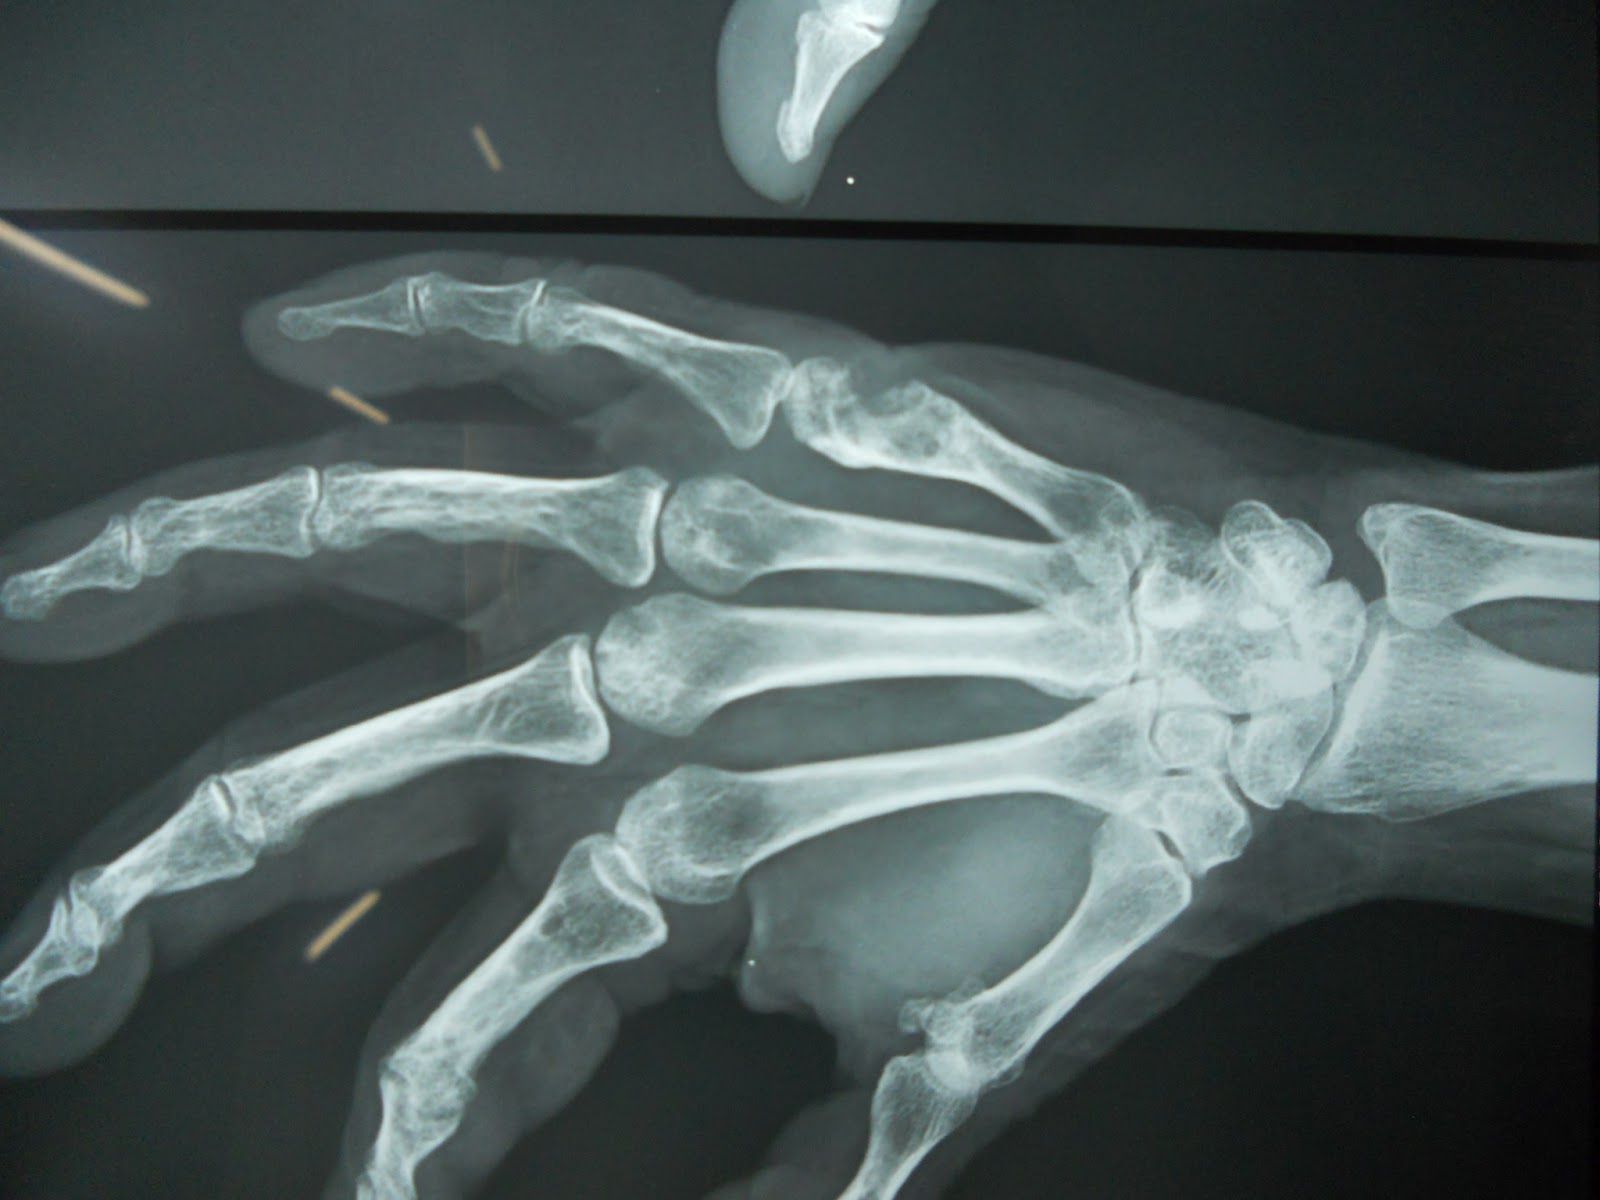

Now the present x rays and clinical photographs show the remarkable recovery of the child and x ray with hardly any evidence of previous pathology.